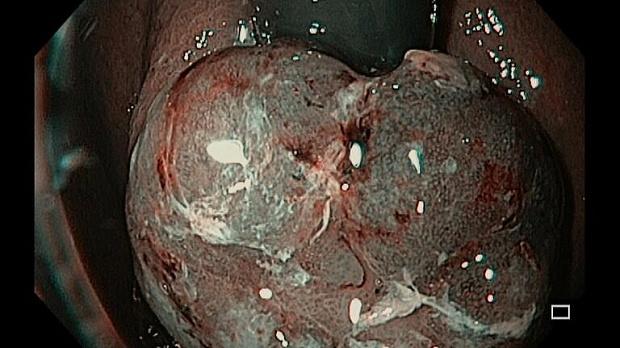

Иллюстрация №1: Рис1. Опухоль кардиоэзофагеального перехода, осмотр из инверсии

При эндоскопическом осмотре в области ПЖП определялась экзофитная опухоль, размерами 20 х 15 мм, на широком основании, высотой до 5-7 мм, с красной шероховатой поверхностью и налетом фибрина (рис. 1). При инструментальной пальпации опухоль легко смещалась, пролабировала в просвет желудка и пищевода. Аксиальная хиатальная грыжа и особенности расположения опухоли в зоне пищеводно-желудочной перехода не позволили создать необходимую акустическую среду и провести мини-зондовое эндоскопическое ультразвуковое исследование.